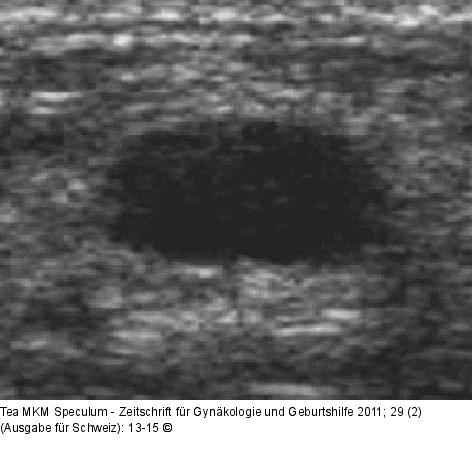

Abbildung 1: Einfache Mammazyste Einfache Mammazyste. |